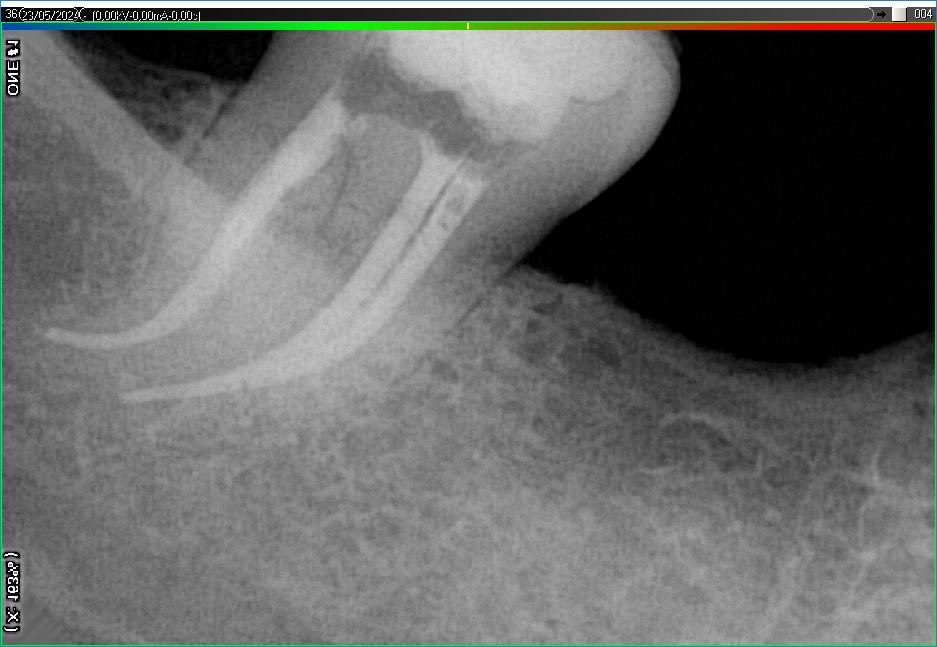

Вилучення інструменту з каналів зуба